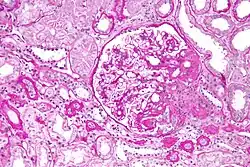

Light micrograph of focal segmental glomerulosclerosis, hilar variant. Kidney biopsy. PAS stain.

On histology, FSGS manifests as scarring (sclerosis) to segments of glomeruli; moreover, only a portion of glomeruli are affected.[7][20][21] The focal and segmental nature of disease seen on histology help to distinguish FSGS from other types of glomerular sclerosis.[21]

Diagnosis of FSGS is made by renal biopsy that includes at least fifteen serial cuts with at least eight glomeruli.[32][33] Histologic features include sclerosis (scarring) of a portion (average: 15%) of the glomerular space, with only a portion of glomeruli manifesting any sclerosis.[33]